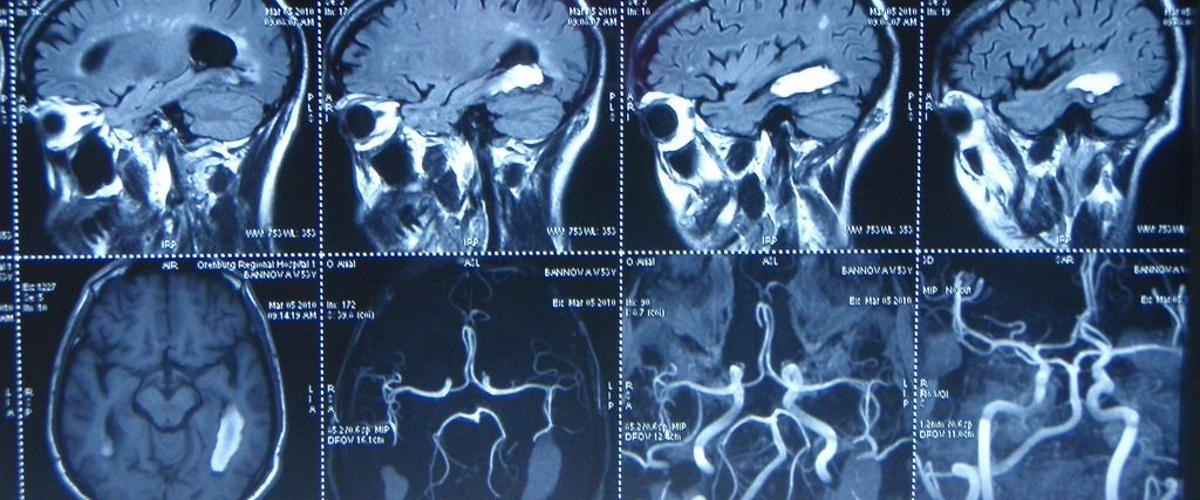

При аневризме головного мозга артерии в нем расширяются, что нередко приводит к смертельному кровоизлиянию. Выявление этого состояния — непростая задача, ведь размеры и формы аневризм значительно различаются. Чтобы поставить диагноз, радиологам приходится просматривать множество снимков.

Обработанные снимки использовались для обучения алгоритма HeadXNet. В результате ИИ научился отмечать полупрозрачным выделением участки, которые считает подозрительными. При этом врач, работающий с алгоритмом, может видеть первоначальный снимок.

В ходе экспериментов восемь врачей испытали HeadXNet на наборе из 115 сканов головного мозга. Алгоритм-помощник позволил им выявить больше аневризм и снизил процент ошибок.